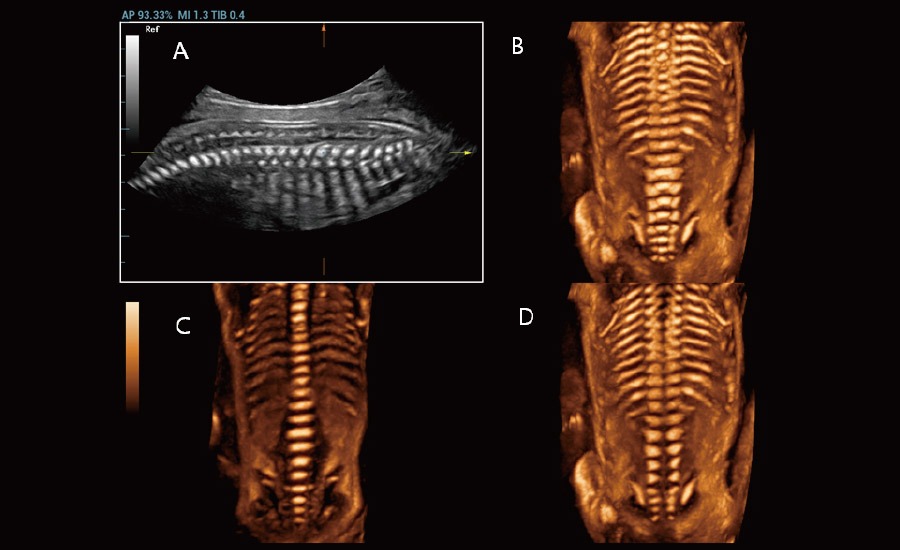

Gra?as Ć revolucionĆ”ria plataforma ZST+, o Nuewa R9 Ć© equipado com tecnologias avan?adas e inovadoras para enfrentar os desafios diagnĆ³sticos na saĆŗde da mulher. Tecnologias revolucionĆ”rias, como a angiografia ultramicroscĆ³pica (UMA), ajudam vocĆŖ a explorar mais microdetalhes e a realidade escondida. Projetado com a inestimĆ”vel sabedoria de especialistas, ele oferece informa??es completas de forma inovadora, que v?o alĆ©m de suas expectativas para diagnĆ³stico com mais confian?a, padroniza??o e eficiĆŖncia frente aos diferentes desafios em ambientes hospitalares exigentes e sobrecarregados.

A tecnologia inovadora elimina as limita??es das tradicionais imagens com Doppler. Com resolu??o espacial e sensibilidade de fluxo ultra-altas, permite a detec??o de perfus?es de fluxos muito sutis e lentos, ampliando assim a aplica??o clĆnica da avalia??o qualitativa e quantitativa do ultrassom no cĆ©rebro fetal, rins, placentas, endomĆ©trios, ovĆ”rios etc.

Por meio da combina??o de algoritmos avan?ados e do conhecimento especĆfico da regi?o, a inovadora solu??o Smart Scene permite a identifica??o automĆ”tica das caracterĆsticas do tecido e fornece diagnĆ³stico especĆfico dos Ć³rg?os com informa??es completas. Com base na identifica??o automĆ”tica de cenĆ”rios, a solu??o realiza n?o apenas a varredura 2D inteligente com configura??es e medidas automĆ”ticas, mas tambĆ©m oferece informa??es 3D abrangentes em todas as etapas, desde a otimiza??o de imagens volumĆ©tricas atĆ© a difĆcil obten??o de planos 2D, e a quantifica??o durante todo o procedimento. Ele ajuda a reduzir em grande parte a dependĆŖncia de habilidades clĆnicas, ao mesmo tempo que aumenta a precis?o, a confian?a e a eficiĆŖncia no diagnĆ³stico.